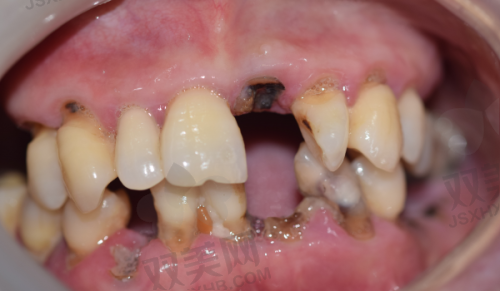

北京瑞鲨口腔医院擅长的项目众多,涵盖了口腔医疗的各个领域。主要包括牙齿矫正、牙齿美白、口腔种植、口腔修复、儿童口腔治疗等。在牙齿矫正方面,医院拥有多种矫正技术,如传统金属矫正、陶瓷矫正、隐形矫正等,能够根据患者的牙齿情况和个人需求,选择更适合的矫正方式。牙齿美白项目采用精良的美白技术和材料,能够快速、安心地改善牙齿颜色,让患者拥有洁白亮丽的牙齿。口腔种植是医院的特色项目之一,医生们具备丰富的种植经验,能够熟练运用各种种植系统,为患者解决牙齿缺失问题。口腔修复项目包括烤瓷牙、全瓷牙、活动假牙等,能够修复牙齿的形态和功能。儿童口腔治疗则针对儿童的口腔特点,提供专精的预防和治疗服务,帮助儿童养成良好的口腔卫生习惯。

医院拥有一支专精的医生团队。这些医生包括正畸医生、种植医生、修复医生等。正畸医生擅长各种牙齿矫正技术,能够根据患者的牙齿畸形情况,制定个性化的矫正方案,帮助患者拥有整齐美观的牙齿。种植医生具备丰富的口腔种植经验,能够熟练掌握各种种植技术,为牙齿缺失患者提供安心、有效的种植修复服务。修复医生则在烤瓷牙、全瓷牙等口腔修复方面有着不错的技艺,能够修复患者牙齿的形态和功能。他们都经过专精的培训和学习,不断提升自己的技术水平,为患者提供优质的医疗服务。